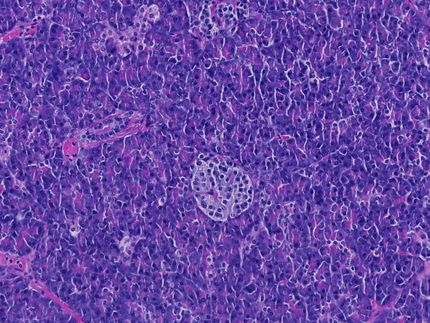

Das Team um Torsten Olszak (jetzt Ludwig-Maximilians-Universität München) und Richard Blumberg (Boston) verglich für die Versuche normale Labormäuse und besonders keimfrei gehaltene Mäuse. «Deren Haltung ist aufwendig, sie leben in extra abgeschotteten Plastikbehältern und erhalten speziell aufbereitetes Futter», sagte Olszak der Nachrichtenagentur dpa. «Es zeigte sich, dass die keimfreien Mäuse besonders viele natürliche Killer-T-Zellen in der Lunge und im Darm haben, die nach Aktivierung eine Reihe von Botenstoffen ausschütten, die bei Autoimmunkrankheiten und Entzündungen eine Rolle spielen.»

Die keimfreien Mäuse waren im Vergleich zu den anderen Labormäusen anfälliger für Asthma und eine der menschlichen Colitis ulcerosa verwandten Darmentzündung. Diese beruhen auf überschießenden Reaktionen des Immunsystems, und wurden von den Wissenschaftlern durch spezielle Stoffe provoziert.